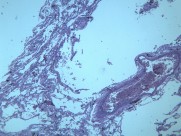

慢性支气管炎(chronic bronchitis)是由于感染或非感染因素引起气管、支气管粘膜及其周围组织的慢性非特异性炎症。其病理特点是支气管腺体增生、粘液分泌增多。临床出现有连续两年以上,每持续三个月以上的咳嗽、咳痰或气喘等症状。早期症状轻微,多在冬季发作,春暖后缓解;晚期炎症加重,症状长年存在,不分季节。疾病进展又可并发阻塞性肺气肿、肺源性心脏病,严重影响劳动力和健康。